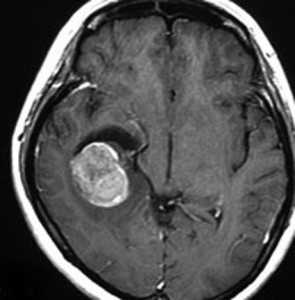

典型的な画像(膠芽腫に近い病理像の例)

特に悪性度の高かったPNETのMRI画像です。病理は膠芽腫に近い組織像でした。この子は4歳でした。小さい子供にできますが発見されたときには巨大な腫瘍になってしまっていることが多いです。この腫瘍の初回手術の時にはあふれるように出血しました。治療は,手術でなるべく全部取らないとなりません。でもこんなに大きいのを手術でいっぺんに取ると命が危ないし,摘出できても障害が大きくなりすぎますから,化学療法や放射線治療で小さくしておいてから,開頭手術で全部摘出するという方法もあります。この子供はそうしました。もし3歳以下だと放射線が使いにくいので化学療法だけになりますが,いずれにしてもPNETの治療は難しいです。

脳脊髄照射と化学療法で抑え込んで,右の写真は治療後10年経ったときのものです。大きくなってからは,高次脳機能障害と難治性てんかんで学校へ通うのが難しくなりました。